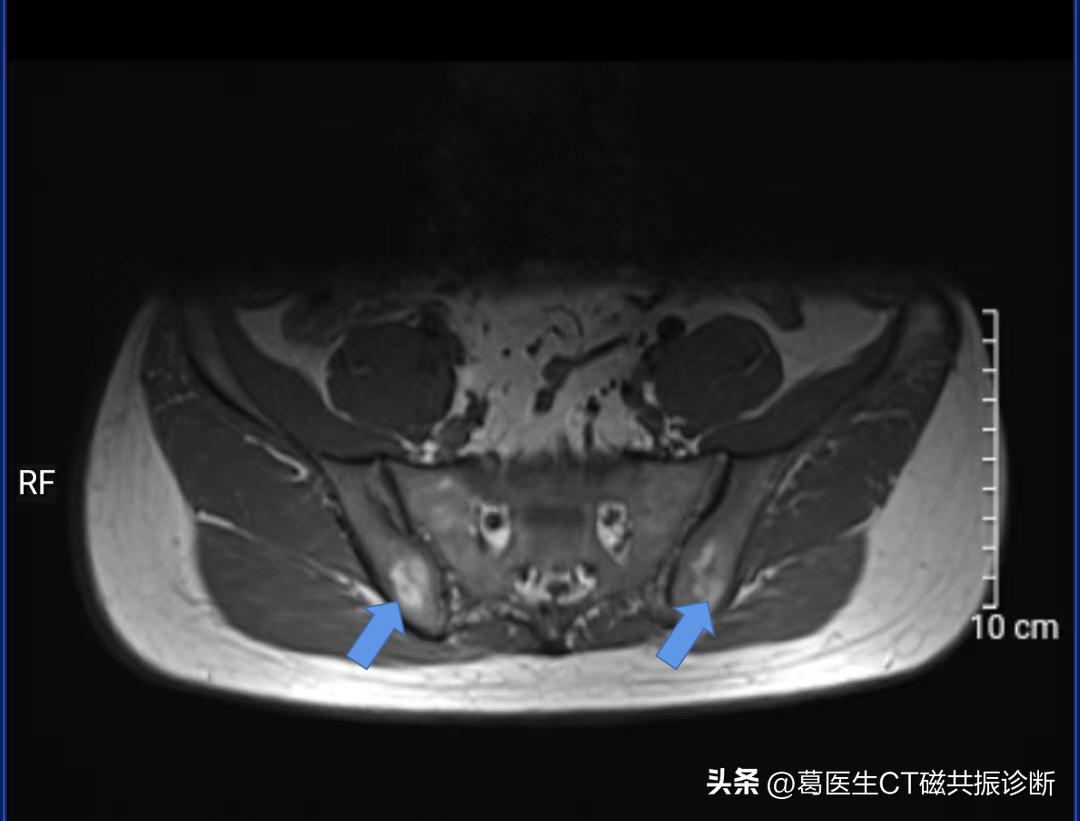

再来一张图片

箭号所指白色区域

因为,磁共振图像中,箭号所指区域(也就是被认为是病灶的地方)为 正常结构,专业上叫 黄骨髓

人的骨头中有红骨髓和黄骨髓,看到图中蓝色箭号为黄骨髓,由于黄骨髓中脂肪含量比较多,磁共振T1序列上表现为 高信号(偏白色)。

甚至都说到 “5岁后髋臼区出现脂肪性骨髓,随着年龄增长,骨盆也包括髂骨出现黄骨髓是正常现象。当然了,某些造血系统疾病或者化疗病人会出现红黄骨髓分布的异常,但你不属于这些情况”,这种类似于影像专业本科教学的内容